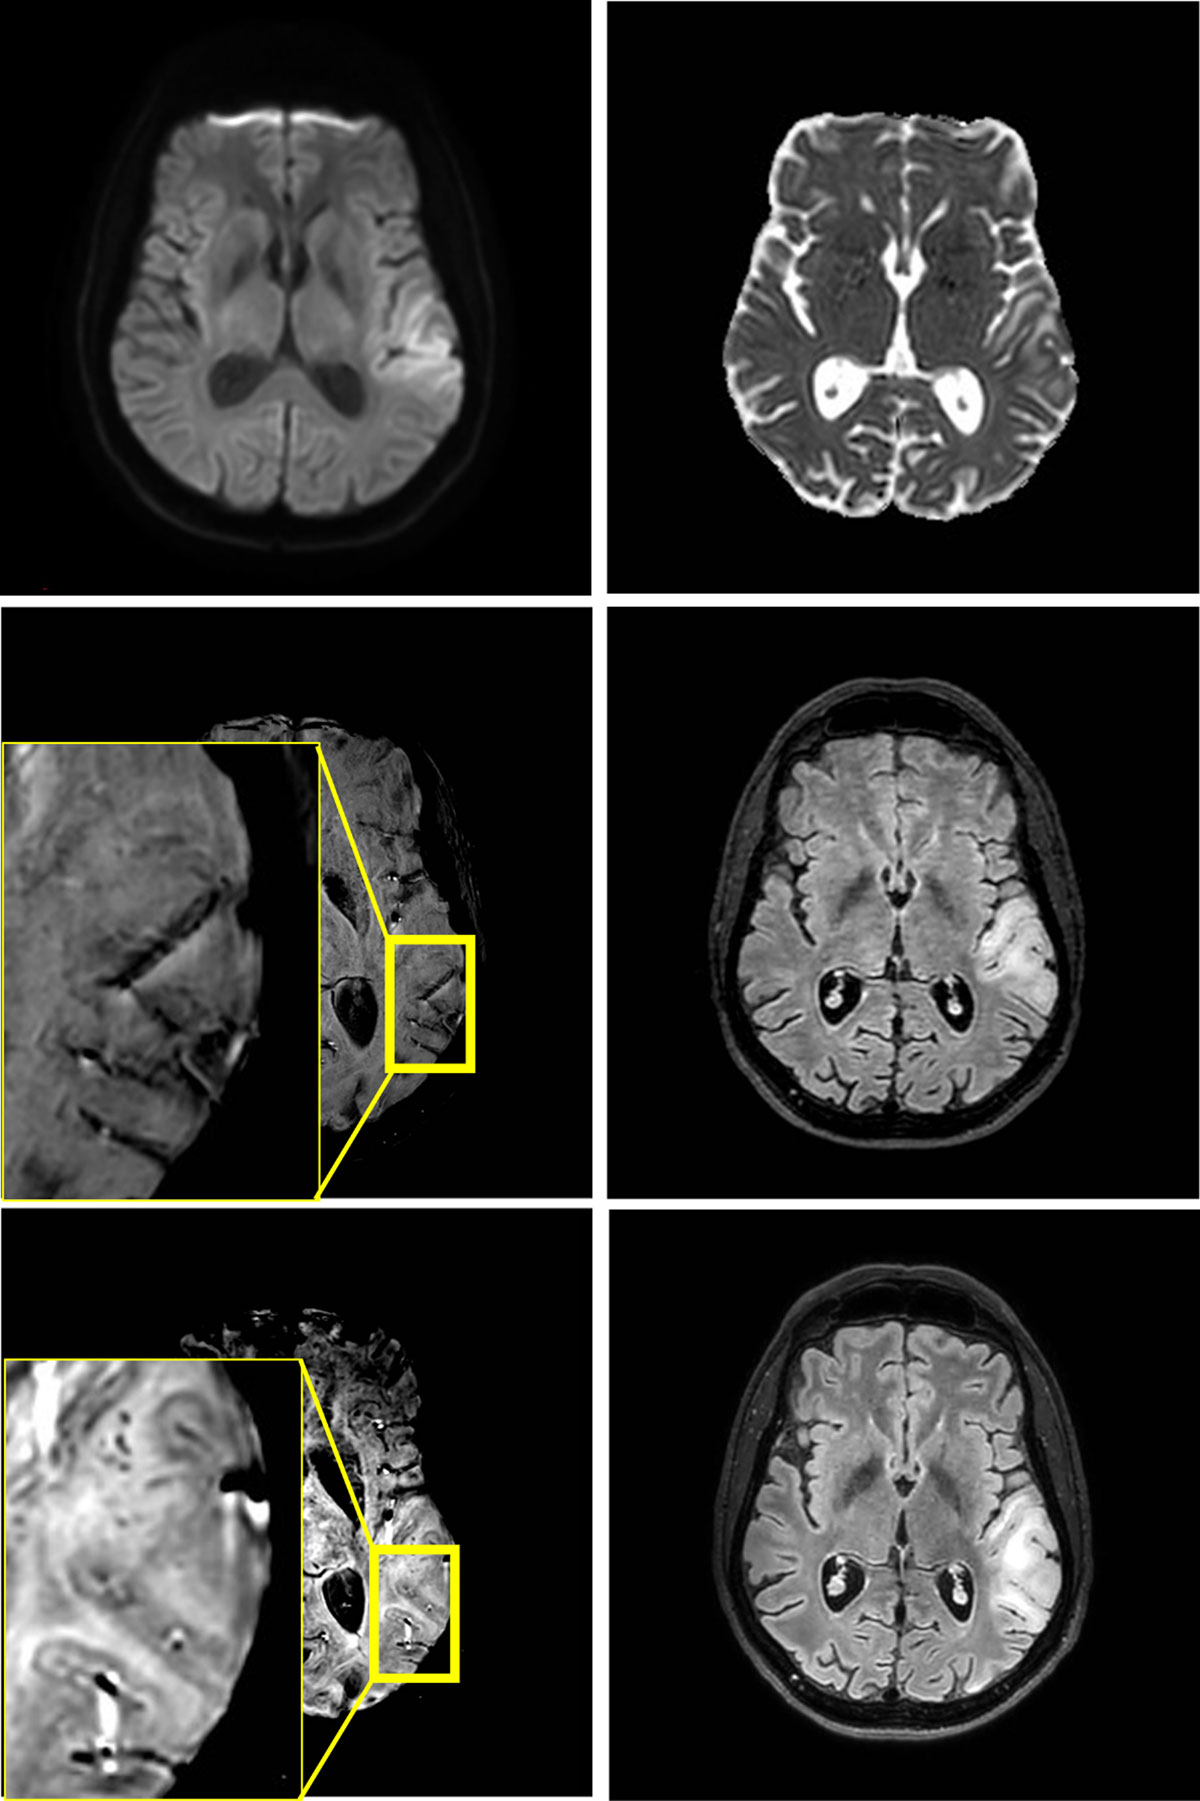

Figure 1

Edema in the left temporoparietal operculum without reduced diffusivity on MRI at 3T at first presentation (4 upper images). No microhemorrhages are found on the first scan, but they are present in juxtacortical location at one-week follow-up (2 lower images).

An immediate computed tomography (CT) and CT angiography (CTA, Siemens) showed corticosubcortical hypodensity in the left temporoparietal operculum, and normal craniocervical arteries. The next day’s MRI (3 Tesla, Philips) showed local corticosubcortical vasogenic edema without reduced diffusion, in keeping with a stroke-like MELAS lesion (Figure 1). Treatment with L-arginine was initiated, and the aphasia improved during hospitalization. A follow-up MRI (3 Tesla, Philips) after one week showed further expansion of the lesion that now demonstrated reduced diffusion as well as multiple, local, juxtacortical microhemorrhages on susceptibility weighted imaging (SWI), of which most were remarkably fine (< 1 mm).